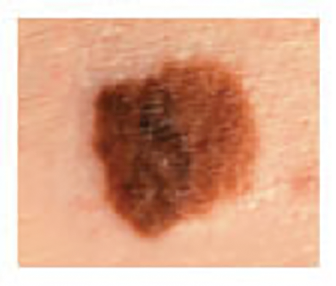

Melanoma Photos

Nodular melanoma on the leg of a Native American woman.

Photo: International Skin Imaging Collaboration

Amelanotic melanomas may be pinkish-looking, reddish, purple, normal skin color or essentially clear and colorless.